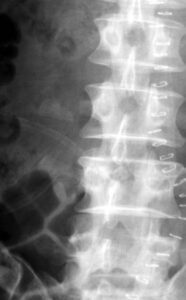

Figure 1b. X-ray image of the lumbar spine (anterior-posterior projection).

If you think that it is a

– congenital alteration,

– rudimentary ribs in the lumbar spine,

– an imitation of thoracic spine created by the lumbar spine,

– “lumbar ribs”

you’re wrong!

You should carefully study this presentation!

The good clinician says: No diagnosis without the patient’s history and

No diagnosies without the clinical picture!

That’s true, but here is one of the few exceptions: The clinical picture takes you sometimes onto the wrong track. –

In the vera first case 1a however, clinical history with a lumbar damage was the cast iron proof for the diagnosis.

The situation was more difficult in case 1b: The patient pretended, he had had no trauma before. He had reasons not to be the person who felt from the roof. His history was misleading.

Carefully repeated anamnesis however revealed a trauma 5 years before. So we assume old transverse process fractures L1-3 left. Bone formations are dislocated caudally from the amputated corresponding transverse processes. They fit together in size and shape for a complete transverse process. Our fist assumption of “lumbar ribs” does not explain the dislocation of fragments and the corresponding diminution of transverse process stumps.